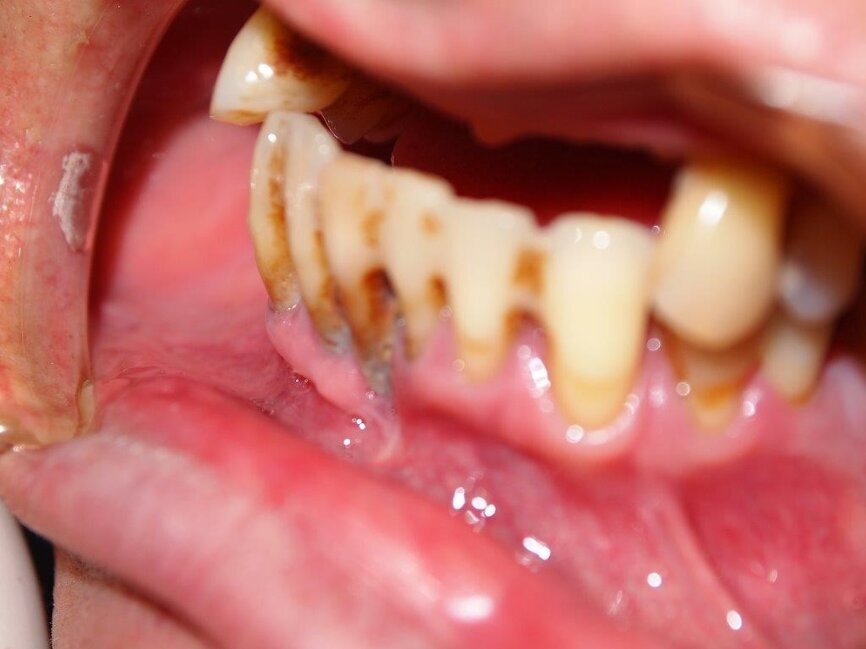

Wykonano CBCT, z którego wynikało, iż pacjent ma chorobę przyzębia. Zakwalifikowano wszystkie 10 zębów żuchwy do ekstrakcji. Zaplanowano zaopatrzenie pacjenta 8 implantami ICX oraz 5 implantami tymczasowymi Alpha Bio w celu wykonania pracy protetycznej tymczasowej bez obciążenia implantów docelowych ze względu na brak kontroli nad pacjentem w okresie wgajania implantów (zdjęcie CBCT oraz wewnątrzustne pacjenta). Za pomocą komputerowego systemu nawigacyjnego 3D został zaprojektowany szablon przytwierdzany 3 pinami do kości żuchwy w celu jego stabilizacji.